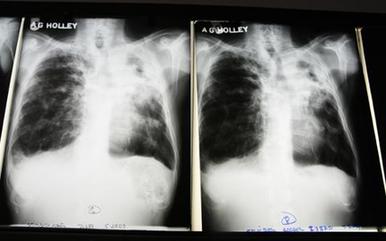

The World Health Organization recently reported that the number of cases of tuberculosis has been falling since 2006. Also, fewer people are dying from TB. But a study by researchers at the University of California, San Francisco, says smoking could threaten this progress.

Efforts to control the spread of tuberculosis have mainly focused on finding and treating infections. Much less effort has been made to understand the causes. Dr Anthony Fauci is the director of the United States National Institute of Allergy and Infectious Diseases.

Smoking does not cause tuberculosis; bacteria cause the infection. But the study says smoking affects the nervous system in a way that makes an inactive case of TB more likely to develop into an active one.